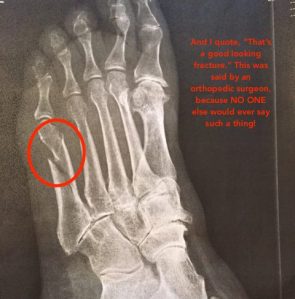

Jean was a trouper — right after it happened, she still went on a limo ride! (We hijacked the kids’ prom limo while they went to dinner — a great tip for all you parents with prom-aged children!) But, she still ended up at urgent care getting a boot and will need to see an orthopedist when she gets home. Silver lining: she’ll get to ride on one of those cool little golf carts at the airport on her way home!